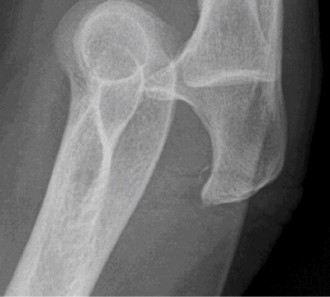

Examination reveals deformity about the elbow with no open lesions or skin tenting. He has a palpable radial and ulnar pulse and is neurologically intact. His images are shown (Figs. 2–85 to 2–88).

Figure 2–85

Figure 2–86

Figure 2–87

Figure 2–88

What is the diagnosis and direction of displacement?

- Monteggia fracture dislocation, posterolateral displacement of the forearm about the humerus

- Simple elbow dislocation, posterolateral displacement of the forearm about the humerus

- Transolecranon complex elbow dislocation

- Simple elbow dislocation, posteromedial displacement of the forearm about the humerus

Discussion

The correct answer is (B). This is the most common type of elbow dislocation, and often does not cause any osseous injury. Posterolateral and posteromedial dislocation account for approximately 90% of dislocations. Adequate pre- and postreduction films are necessary to evaluate for fracture, which would change the classification to a complex injury.